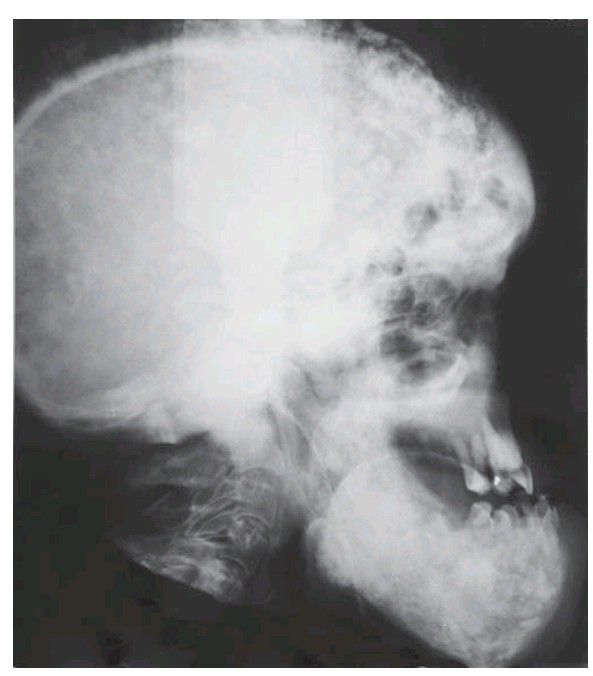

Paget’s disease.

A very severely affected individual with extensive sclerosis and enlargement of all skull bones and jaws including, unusually, the mandible.